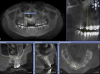

Ашот Опубликовано 8 октября, 2012 Поделиться Опубликовано 8 октября, 2012 Уважаемые коллеги, ситуация в следующем. Я хирург, хочу услышать мнение ортодонтов.Пациент 25 лет. Зуб 53 удален в детстве. В 23 года начал носить брекеты, пытались сначала свести 14,12. Затем решили развести 12,14, с последующим наращиванием кости в области 13 и имплантацией. Все это прошло безуспешно, графт не прижился. На данный момент пациента ведем мы.Вопросы:1) возможно ли вытянуть этот клык?2) вестибулярно или небно лучше раскрыт? Сразу оговорюсь, вестибулярно попытался открыть, но наклон большой и ортодонт не решился прицепить тягу. Теперь просит открыть небно, но не уйдет ли кость, оставшаяся незначительно небно? Спасибо. 1 Ссылка на комментарий

TiAn Опубликовано 9 октября, 2012 Поделиться Опубликовано 9 октября, 2012 Кость уйдет небная, конечно. Мне кажется, это не очень благоприятное положение зуба, слишком сильный угол к основной оси зубов 11 и 12. Ссылка на комментарий